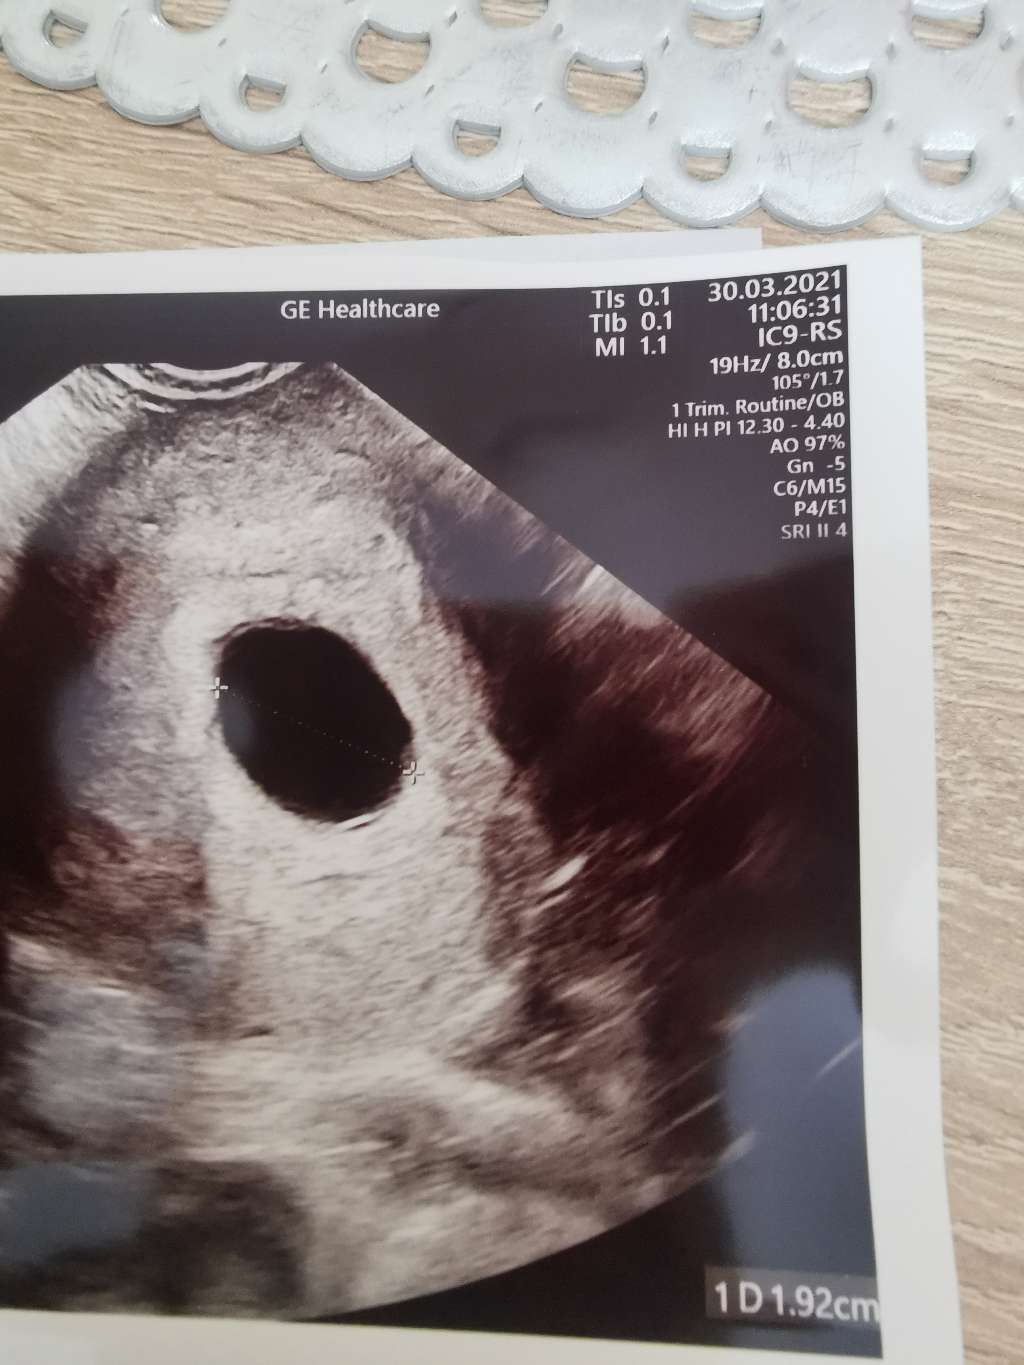

Ciąża 6/7 TC brak zarodka

Niestety się nie udało, pusto tak jak widać. Czekamy na poronienie, kolejna wizyta 8 kwietnia, do tego czasu lekarz ma nadzieję, że poronie sama i nie będzie trzeba wysyłać mnie do szpitala. Póki beta rośnie i pęcherzyk nie osiągnął jeszcze 25 cm, to on ma związane ręce i nie może nic zrobić, w szpitalu również nikt się nie podejmie zabiegu ani podania tabletki przez te właśnie 2 rzeczy. Cieszę się, że się na to przygotowałam i nie szłam tam z nastawieniem, że wszystko będzie super, bo bolałoby chyba 10 razy bardziej. Dobrze, że wiem na czym stoję i na co czekam. Już przynajmniej nie będę się łudzić. Mam odstawić wszystkie leki oprócz witamin i w czwartek zrobić betę, mam nadzieję że zacznie spadać, bo wtedy niby organizm przygotowuje się do poronienia. Liczę na to, że poronie sama w domu przy mężu, a nie w szpitalu z obcymi ludźmi. Dziękuję Wam dziewczyny za wsparcie. ❤️